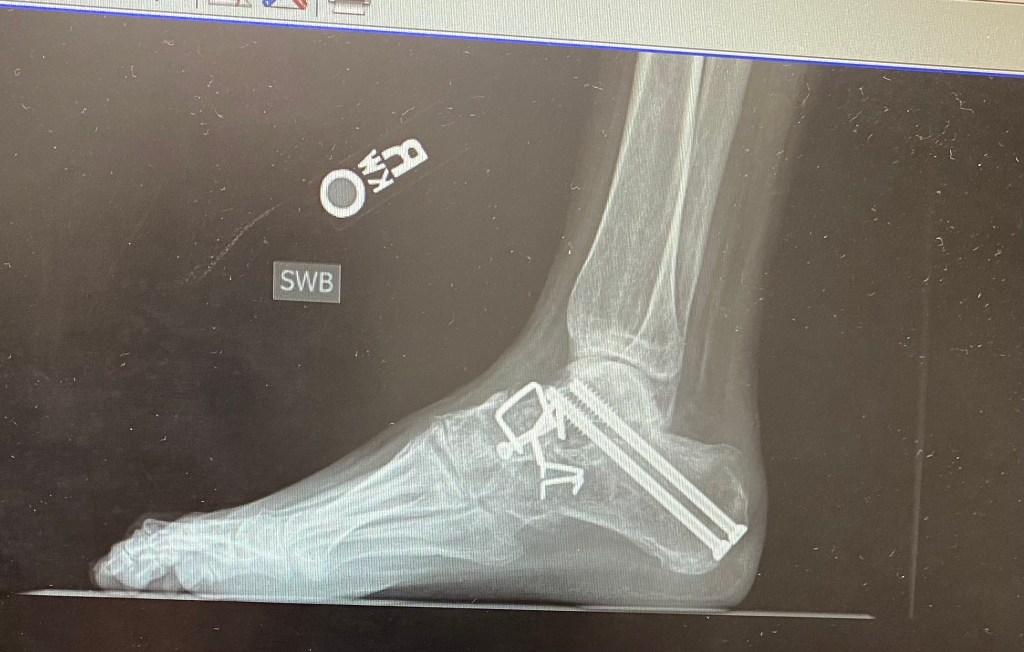

The only logical solution, in this doctor’s opinion was corrective surgery. So in early November of last year I had yet another major surgery. Hardware was removed, joints cleaned up, new hardware installed, even had a major nerve severed with the hopes of diminishing the pins and needles pain of neuropathy. I spent just shy of 11 weeks in a cast and on crutches. Fast forward to this past week…I’m in a boot and trying to wean off of crutches. It has been a struggle physically, mentally, and emotionally. Due to some fairly intense, weight bearing pain and lots of uncertainty, I called the doctor. He expressed no concerns about healing as x-rays just two weeks ago confirmed I am healing well. He did recommend I take it easy for a few days and give my foot a rest. I feel a bit of relief (mentally) and am praying the emotional roller coaster I have been on will find the straight smooth path to an exit. I do my best to have a positive attitude and trust God, even though I don’t see my good Doctor’s long term plan.